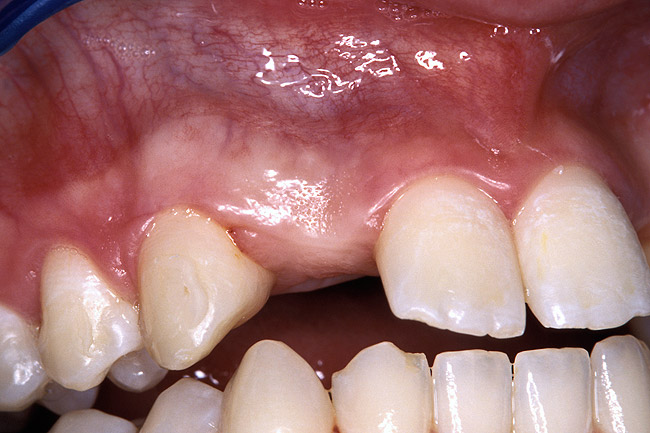

Before the day of surgery, the patient was seen by the orthodontist for the removal of the orthodontic brackets. The patient still was not pleased with the position of the two centrals, and it was determined that this would be addressed after implant placement (Figure 13A). The anatomical variations of the crestal tissue and lack of interdental papilla can be appreciated in the close-up views of the right and left sites (Figure 13B and 13C). There were no surprises on the day of surgery as all of the decisions were made during the planning phase, before the scalpel ever touched the patient. The occlusal view of the CT 3D model revealed the wider alveolar ridge on the right side and thinner crest on the left side (Figure 14A). This was confirmed when the full thickness mucoperiosteal flaps were elevated, and the underyling bone revealed (Figure 14B). The tooth-borne templates were designed to facilitate the drills and drilling sequence specific to the diameters of the predetermined implants (Figure 15A). Each template contained an embedded 5-mm long stainless steel tube, which was approximately 0.2-mm wider than each drill (just wide enough to allow for the drills to rotate freely). Once positioned over the natural teeth, the template was secure and offered precision accuracy in transferring the implant locations from the original software-designed plan, allowing the potential for internal and external irrigation (Figure 15B). The 3.7-mm diameter Tapered Screw-Vent implant drilling sequence requires three drills: pilot, intermediate, and final sizing. Thus, three separate templates were fabricated to a.commodate these sizes. The templates were removed easily and replaced with the next sequential size in less time than it takes to change the drill on the surgical handpiece. After the osteotomies had been.completed, the implants were delivered to the site (Figure 16A and Figure 16B). For this internal hex connection implant, the author r.commends that the flat of the antirotational hex be positioned to the facial for proper orientation of the restorative.components (Figure 17A). Preprepared margins were created from a milled titanium fixture mount transfer post, which was delivered to the implant as support for an immediate transitional restoration. The facial “dot” helped confirm the orientation of the abutment to the facially positioned flat side of the internal hex connection (Figure 17B). Before cementation of the transitional acrylic restorations, a closed-tray, fixture-level impression was made, and a soft-tissue model fabricated.

Figure 13a  Before implant surgery, the orthodontic brackets were removed, revealing (A) the position of the centrals, and (B, C) the anatomical variations of the crestal tissue and lack of interdental papilla.

Figure 13a

Figure 13b  Before implant surgery, the orthodontic brackets were removed, revealing (A) the position of the centrals, and (B, C) the anatomical variations of the crestal tissue and lack of interdental papilla.

Figure 13b

Figure 13c  Before implant surgery, the orthodontic brackets were removed, revealing (A) the position of the centrals, and (B, C) the anatomical variations of the crestal tissue and lack of interdental papilla.

Figure 13c